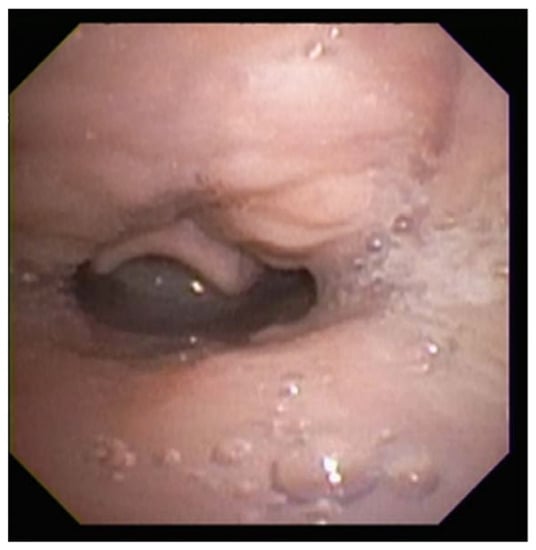

2.12.2. Choanal Atresia